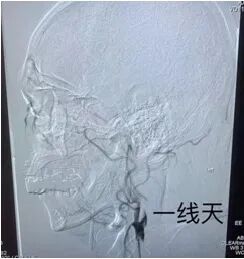

術(shù)中造影顯示:右側(cè)頸內(nèi)動脈狹窄,狹窄率95%。醫(yī)生在陳阿姨的頸動脈中應用球囊擴張植入支架的方法,打通了患者狹窄的血管,避免了腦卒中的發(fā)生。該介入術(shù)創(chuàng)傷小、操作簡單、起效快、恢復快,是目前較為先進的治療方式。